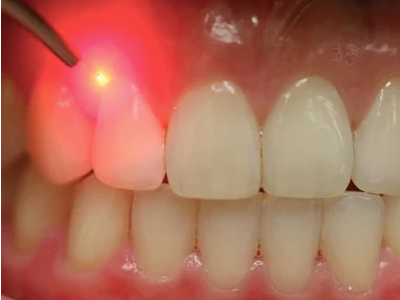

LASER stands for Light Amplification by the Stimulated Emission of Radiation. The instrument creates light energy in a very narrow and focused beam. This narrow focused beam produces a reaction when it hits the tissue, allowing it to remove or shape the tissue.

• Treating gum diseases

- Less Bleeding, More Comfort: The laser’s heat seals blood vessels as it works. Result? Less bleeding during and after your procedure. It’s a cleaner, more comfortable experience all around.

- Lower Infection Risk: As they go, lasers sterilize. This is a neat truth. This considerably reduces the possibility of bacterial infections, improving operation safety and healing.